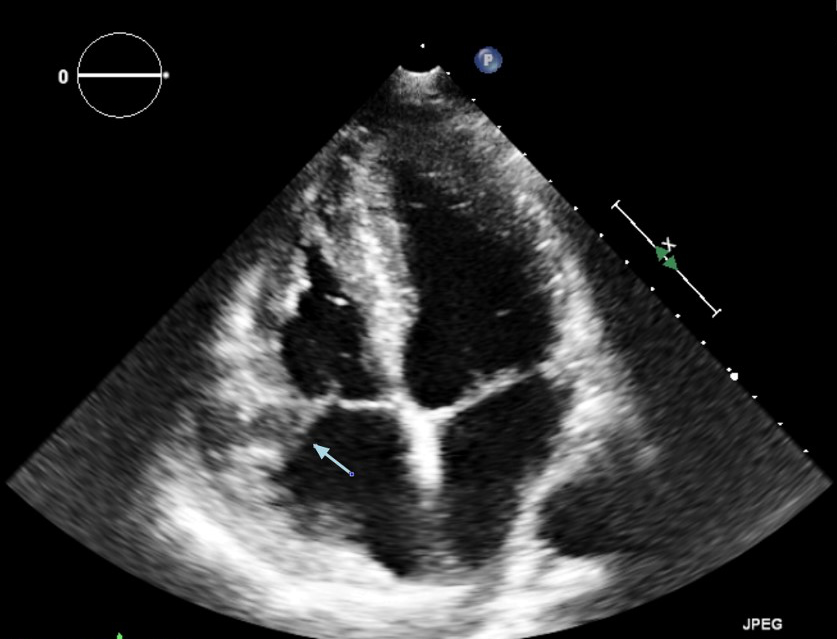

L'ecocardiogramma transtoracico (ETT) mostrava una grande massa isoecogena, non mobile, che occupava quasi interamente l'atrio destro, coinvolgeva la valvola tricuspide, che appariva funzionalmente stenotica, e si estendeva al tratto d’afflusso del ventricolo destro (Figura 1).

linfoma_cardiaco_1.jpg

Figura 1

In merito alla diagnosi differenziale, i reperti ecocardiografici che suggerivano un tumore cardiaco maligno erano la posizione atriale e ventricolare destra della massa, la sua grande dimensione, la sua ampia base di impianto e il coinvolgimento della valvola tricuspide.